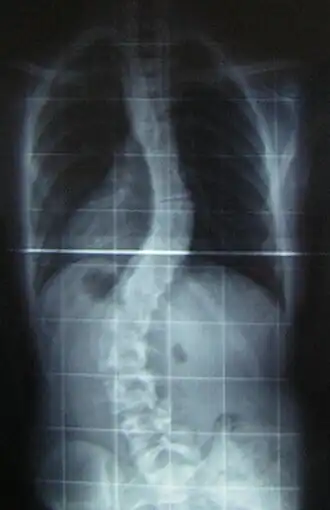

Description de cette image, également commentée ci-après

Radiographie d'un patient atteint de double scoliose.